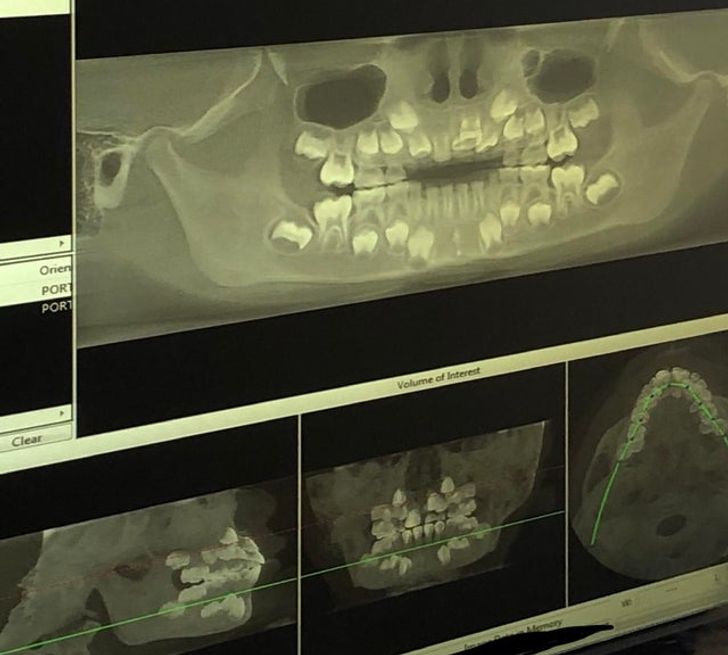

1. A 3D X-ray that shows both milk and adult teeth

Illustration de l'article : 14 X-ray images that reveal a hidden story

© Strictlyforbargain85 / Reddit